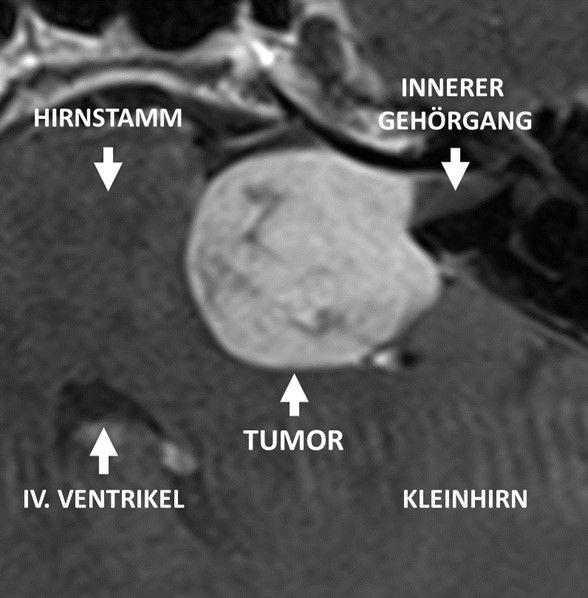

Das Vestibularisschwannom ist ein gutartiger Tumor am Gleichgewichts- und Hörnerv. Die Inzidenz von Vestibularisschwannomen liegt bei 1 Fall pro 100.000 Einwohnern pro Jahr. Damit ist das Vestibularisschwannom (auch als Akustikusneurinom (AKN) bezeichnet) zwar der häufigste Tumor im Kleinhirnhirnbrückenwinkel, im Vergleich zu anderen Erkrankungen handelt es sich aber um eine relativ seltene Tumorart. Das Vestibularisschwannom geht von den Schwann-Zellen des vestibulären Anteil des Nervus vestibulocochlearis (8. Hirnnerven) aus, der Informationen vom Gleichgewichtsorgan an das Gehirn vermittelt. Die klassischen Beschwerden bei Vorliegen eines Vestibularisschwannoms sind Schwindel, Hörminderung und Tinnitus. Aufgrund des Leitsymptoms eines Hörsturzes ging man früher davon aus, dass der Tumor vom Hörnerven ausging.